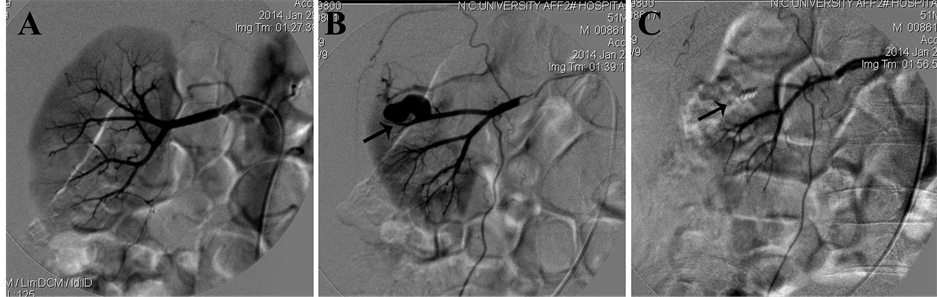

After informed consent was obtained from the patient and his immediate family members, digital subtraction angiography (DSA, OEC9800 C-arm X-ray system, GE, USA) of bilateral renal arteries was performed through right femoral artery using a 6F, 40-cm Flexor Check-Flo sheath and 5F Cobra catheter (Cook Medical, Bloomington, IN). For the first subtraction angiography of right renal artery, no signs of renal artery renal hemorrhage were found and the renal artery system seems intact for the right renal (Figure 2(A)). However, an obvious severe bleeding from the inferior right accessory renal artery at the lower pole of the right renal was found (Figure 2(B)). After the application of the accessory renal artery embolization with gelatin sponge particles and two fibered platinum coils, bleeding was stopped indicated by subtraction angiography (Figure 2(C)) and hemoglobin returned to normal in 7 days after surgery. Furthermore, the DSA images showed that the left renal has also double renal arteries origin from the descending aorta (Figure 3(A) and Figure 3(B)).

Figure 2. Images from right renal arteriography. (A) Without renal blood flow of right renal in the first DSA image; (B) The arrow points to an accessory renal artery from abdominal aorta with bleeding in the lower pole of right kidney; (C) The right accessory renal arterial bleeding stopped after vascular embolization with gelatin sponge particles and fibered platinum coils (arrow).